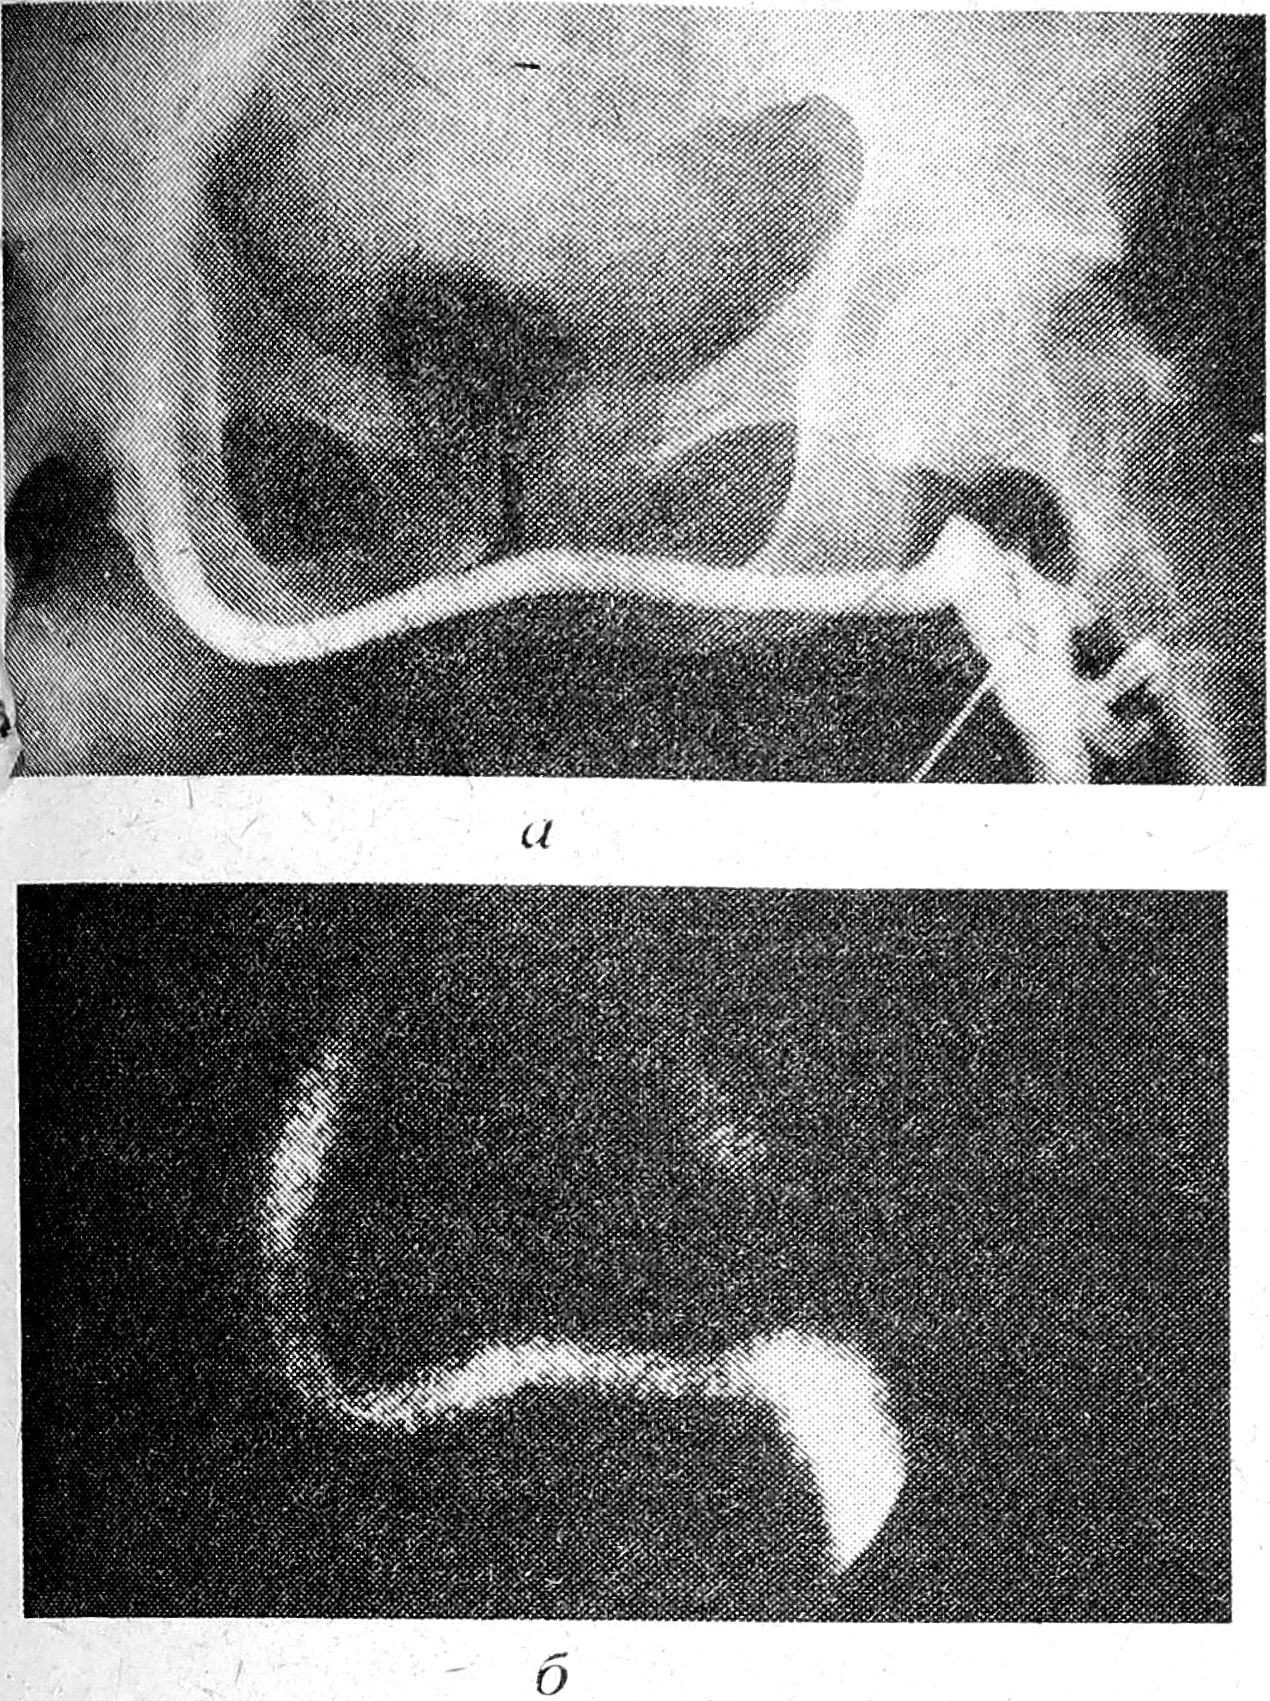

Исследования проводили в положении больного лежа на сцинтилляционной гамма-камере МВ-9100 (ВНР), имеющей параллельный коллиматор с высоким разрешением и диаметр кристалла, равный 33 см. Индикатор (1 мл пертехнетата 99мТс активностью 100 МБк) вводили болюсом в подкожную вену тыла стопы оперированной конечности путем венепункции (чаще) или катетеризации (болюс радиоактивного вещества проталкивали дополнительным введением 10 мл физиологического раствора). Жгут над лодыжками не накладывали. Детектор камеры устанавливали над зоной реконструкции так, чтобы центр его совпадал с проекцией шунта. Регистрацию флебосцинтиграмм производили на поляроидной пленке при счете импульсов 100 тыс. на первой минуте после введения изотопа в вену стопы. Флебосцинтиграммы визуализировать в виде четкой полосы сцинтилляций, повторявшей характерную конфигурацию шунта (см. рис.).

Рис. 1. Флебограмма перекрестного бедренно-бедренного аутовенозного шунта: а) рентгеноконтрастная, б) радиоизотопная.

Данные радиоизотопной флебографии верифицировали результатами рентгеноконтрастной флебографии у всех оперированных больных. Совпадение составило 100%. Столь высокая информативность метода при оценке проходимости, например, перекрестных бедренно-бедренных аутовенозных шунтов связана с техническими особенностями выполнения операции — перевязкой общей бедренной вены больной конечности над шунтом, ликвидацией коллатеральных конкурирующих путей оттока.